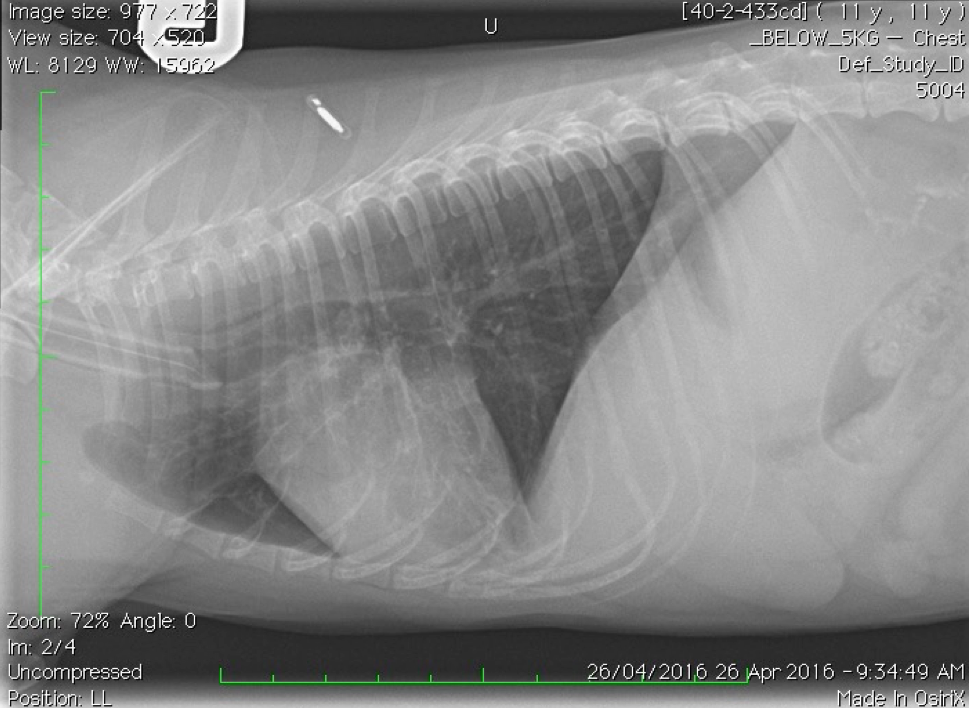

Which lung pattern is shown here?

Mixed alveolar and interstitial

We can see air bronchograms.

There is border obliteration of the diaphragm.

There is a generalised increase in radiodensity throughout the lungs.